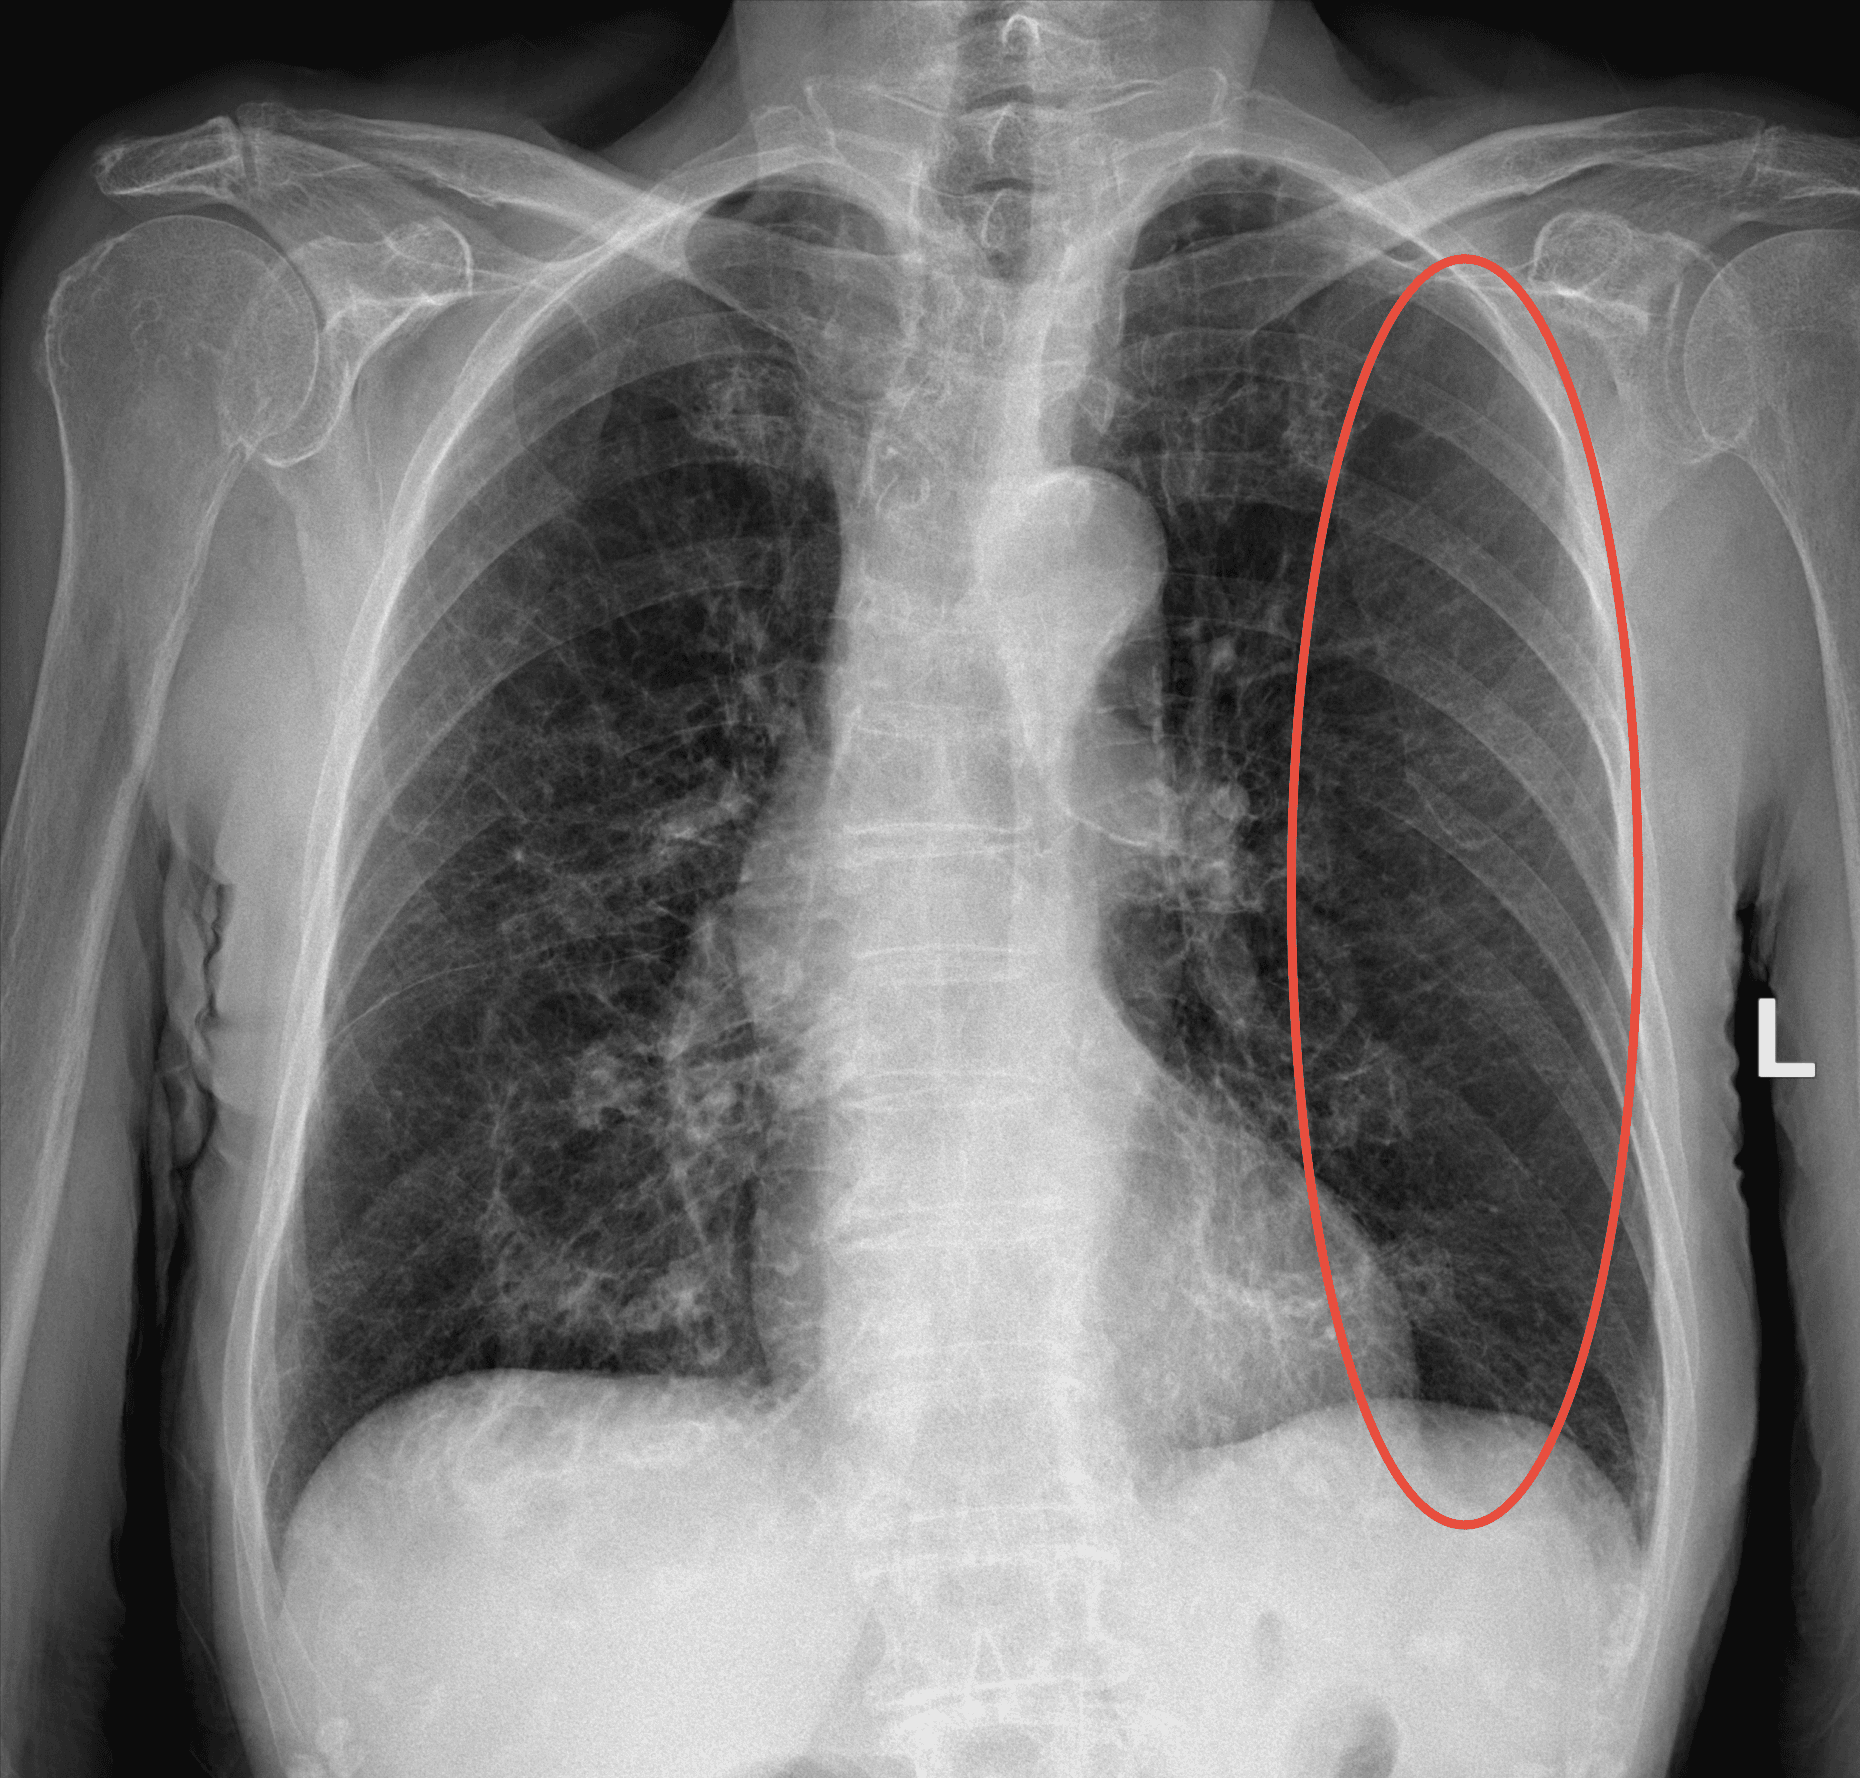

98% certainty

Medusa detected Emphysema in the lungs